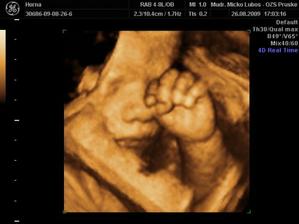

Náš novembrový darček

Na našom drobčekovi sme začali s drahým pracovať v januári. Posledné lieky som vysadila po Silvestri 2008 a vo februári sme splodili náš malý pokladík. Ani som neverila, že to pôjde tak rýchlo. Strašne sa obidvaja tešíme na malého a celé tehotenstvo je pre mňa jeden veľký zázrak.

Našťastie som nemala žiadne komplikácie akurát teraz ku koncu už mi tvrdne bruško. Tak musíme papať lieky a veľa veľa oddychovať. Náš termín 14.11. sa blíži tak sa snažím v kľude študovať múdru literatúru a pomaly sa pripravujem na môj prvý pôrod 🙂)